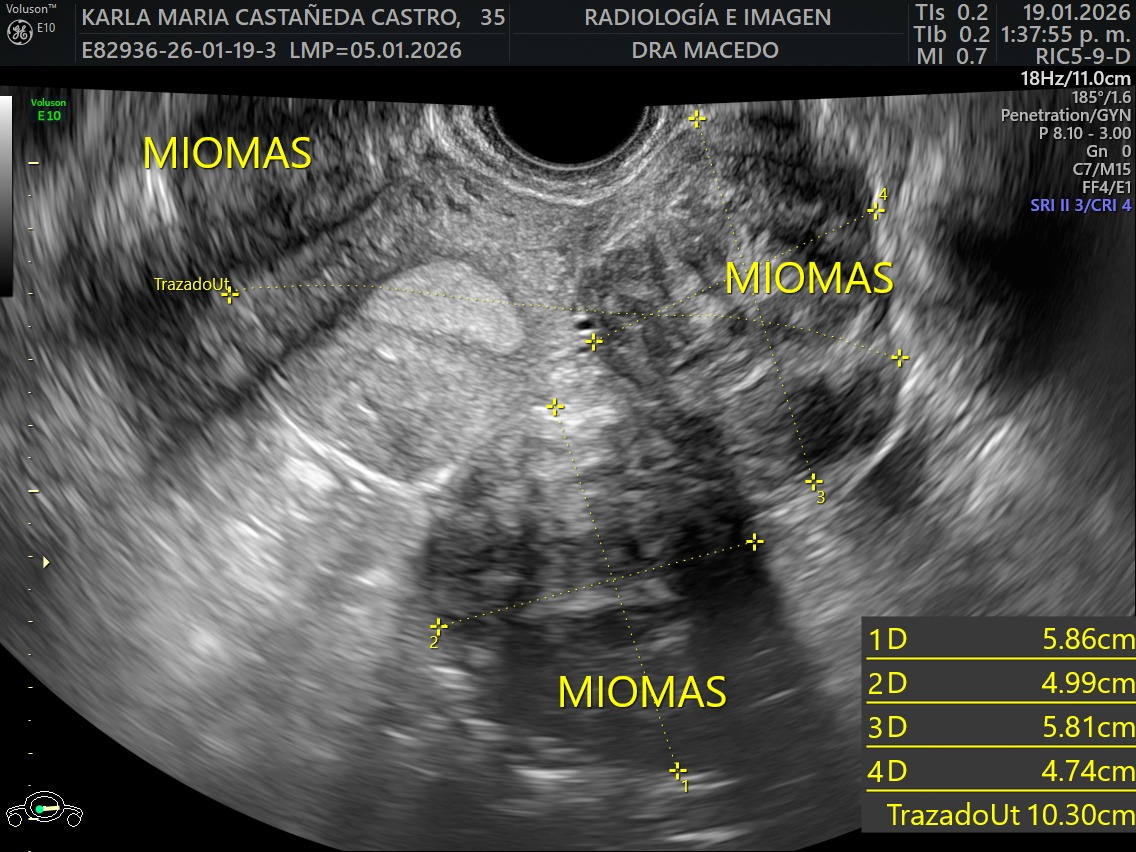

I was recently diagnosed with 16 large uterine fibroid tumors (myomas). My doctors have told me that I need immediate major surgery to remove them. The procedure I will undergo is an Open Abdominal Myomectomy, along with a biopsy to ensure there are no cancerous cells. I will also need to stay in the hospital for approximately five days during recovery. Although even if the tumors are benign, they are putting extreme pressure on my surrounding organs causing significant pain, bleeding, fatigue, and health related issues on a daily basis.

Now, in 2025, doctors have found 16 new tumors, and they’ve advised that surgery must happen as soon as possible. As an artist, my work is my passion and my livelihood, but right now my body simply isn’t keeping up. This has deeply affected my health, my ability to work, and my daily life.

Recientemente me diagnosticaron 16 tumores de fibromas uterinos (miomas). Mis médicos me han informado que necesito una cirugía mayor inmediata. El procedimiento al que me someteré es una miomectomía abdominal abierta, junto con una biopsia para asegurar que no haya células cancerosas. También necesitaré permanecer en el hospital aproximadamente cinco días durante la recuperación. Aunque los tumores de miomas parecen ser benignos, están ejerciendo una presión extrema sobre mis órganos que los rodean, causando dolor significativo, sangrado, fatiga y problemas de salud a diario.

Ahora, en 2025, los médicos han encontrado 16 nuevos tumores grandes y me han indicado que la cirugía debe realizarse lo antes posible. Esto ha afectado profundamente mi salud, mi capacidad para trabajar y mi vida diaria. Como artista, mi trabajo es mi pasión y mi sustento, pero en este momento mi cuerpo simplemente no puede seguir el ritmo.